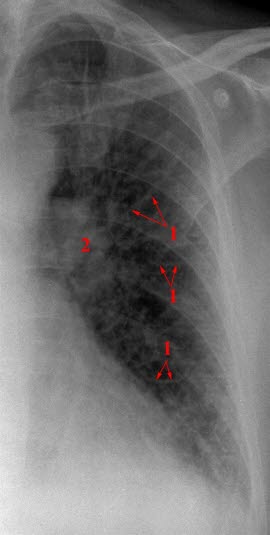

Hjertesvikt, moderat

Utvidete, uskarpt avgrensede lungekar (2) og fortykkede interstitielle septa (1).